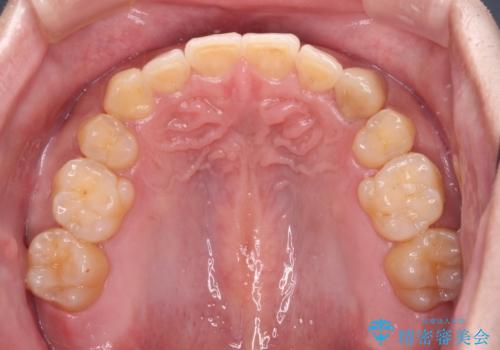

上顎のみの抜歯矯正をインビザラインで行う場合、奥歯の前方移動がインビザラインでは苦手のため、奥歯の咬み合わせが不十分となることがあります。

今回の治療では終了時に奥歯は接触しているものの、接触の程度は物足りないものがある状態でした。今後保定期間に少しずつ奥歯の咬合を改善させていくことになります。